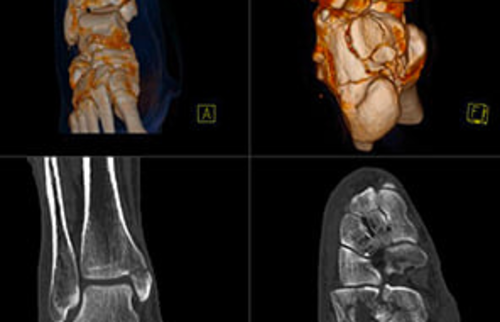

Eine 3D-Rekonstruktion einer Computertomographie (CT) eines Hüftgelenks.

Abbildung 1.

Ansichten einer Computertomographie (CT) eines Fußes und Sprunggelenks.

Abbildung 2.